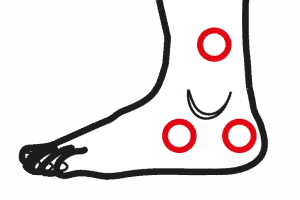

Gonartrosi femoro tibiale

Il ginocchio è una struttura complessa e fondamentale del nostro corpo. Collega la coscia e la gamba, permettendoci di muoverci liberamente. La cartilagine articolare svolge un ruolo primario in quest’area, proteggendo e ammortizzando le ossa degli arti inferiori durante i movimenti. La struttura anatomica del ginocchio Il ginocchio si compone di due articolazioni principali: la prima … Continued